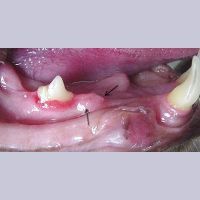

Image 7.1. 2단계 FORL

Image 7.2. Odontoclastic resorptive lesion (class 2)

2단계 FORL 에나멜과 상아질에 침투

왼쪽 상단 네번째 소구치(작은 어금니) FORL